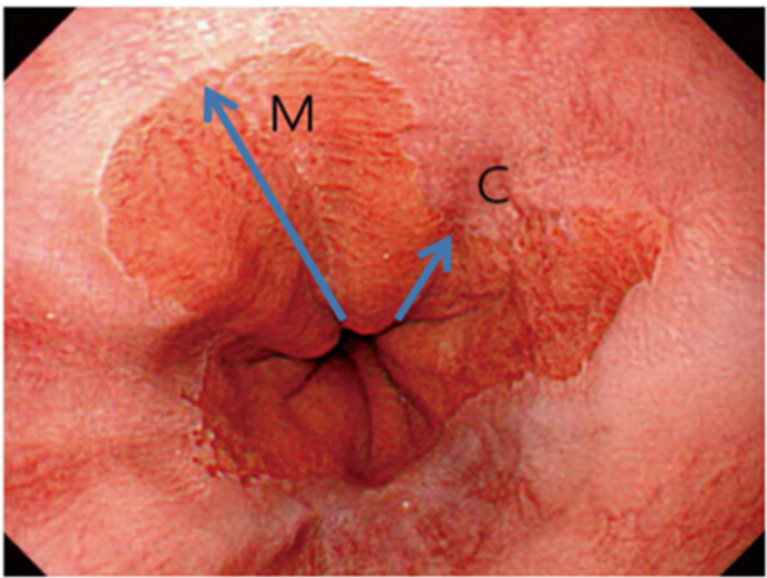

Gjengitt fra Meining et al. (2024). Copyright Endoscopy Campus 2024. Gjengitt med tillatelse i 2025.

Ved gastroskopi må CM-klassifikasjonen anvendes (Praha kriteriene), der C er sirkulær og M maksimal utbredelse. Funnet må dokumenteres med et bilde der også lokaliserte forandringer innenfor BØ dokumenteres og angis etter Paris klassifikasjonen. Ved BØ skal synlige forandringer biopseres, fulgt av 4-kvadrant biopsier hver 2. cm innenfor BØ på nummererte glass.